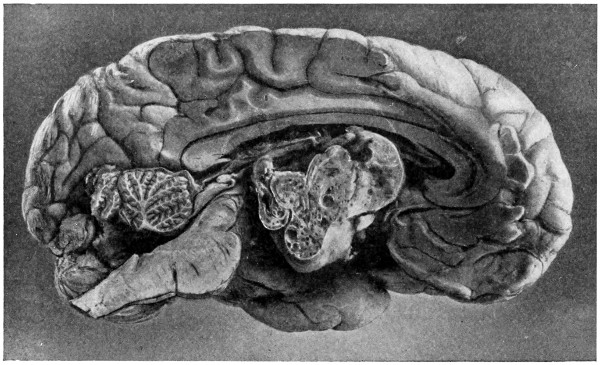

62. A glioma of the brain 211

63. A sarcoma of the brain 211

64. An endothelioma of the dura mater 212

65. A fibroma of the dura mater 212

66. An acoustic tumour 213

67. Symmetrical tuberculomata 214